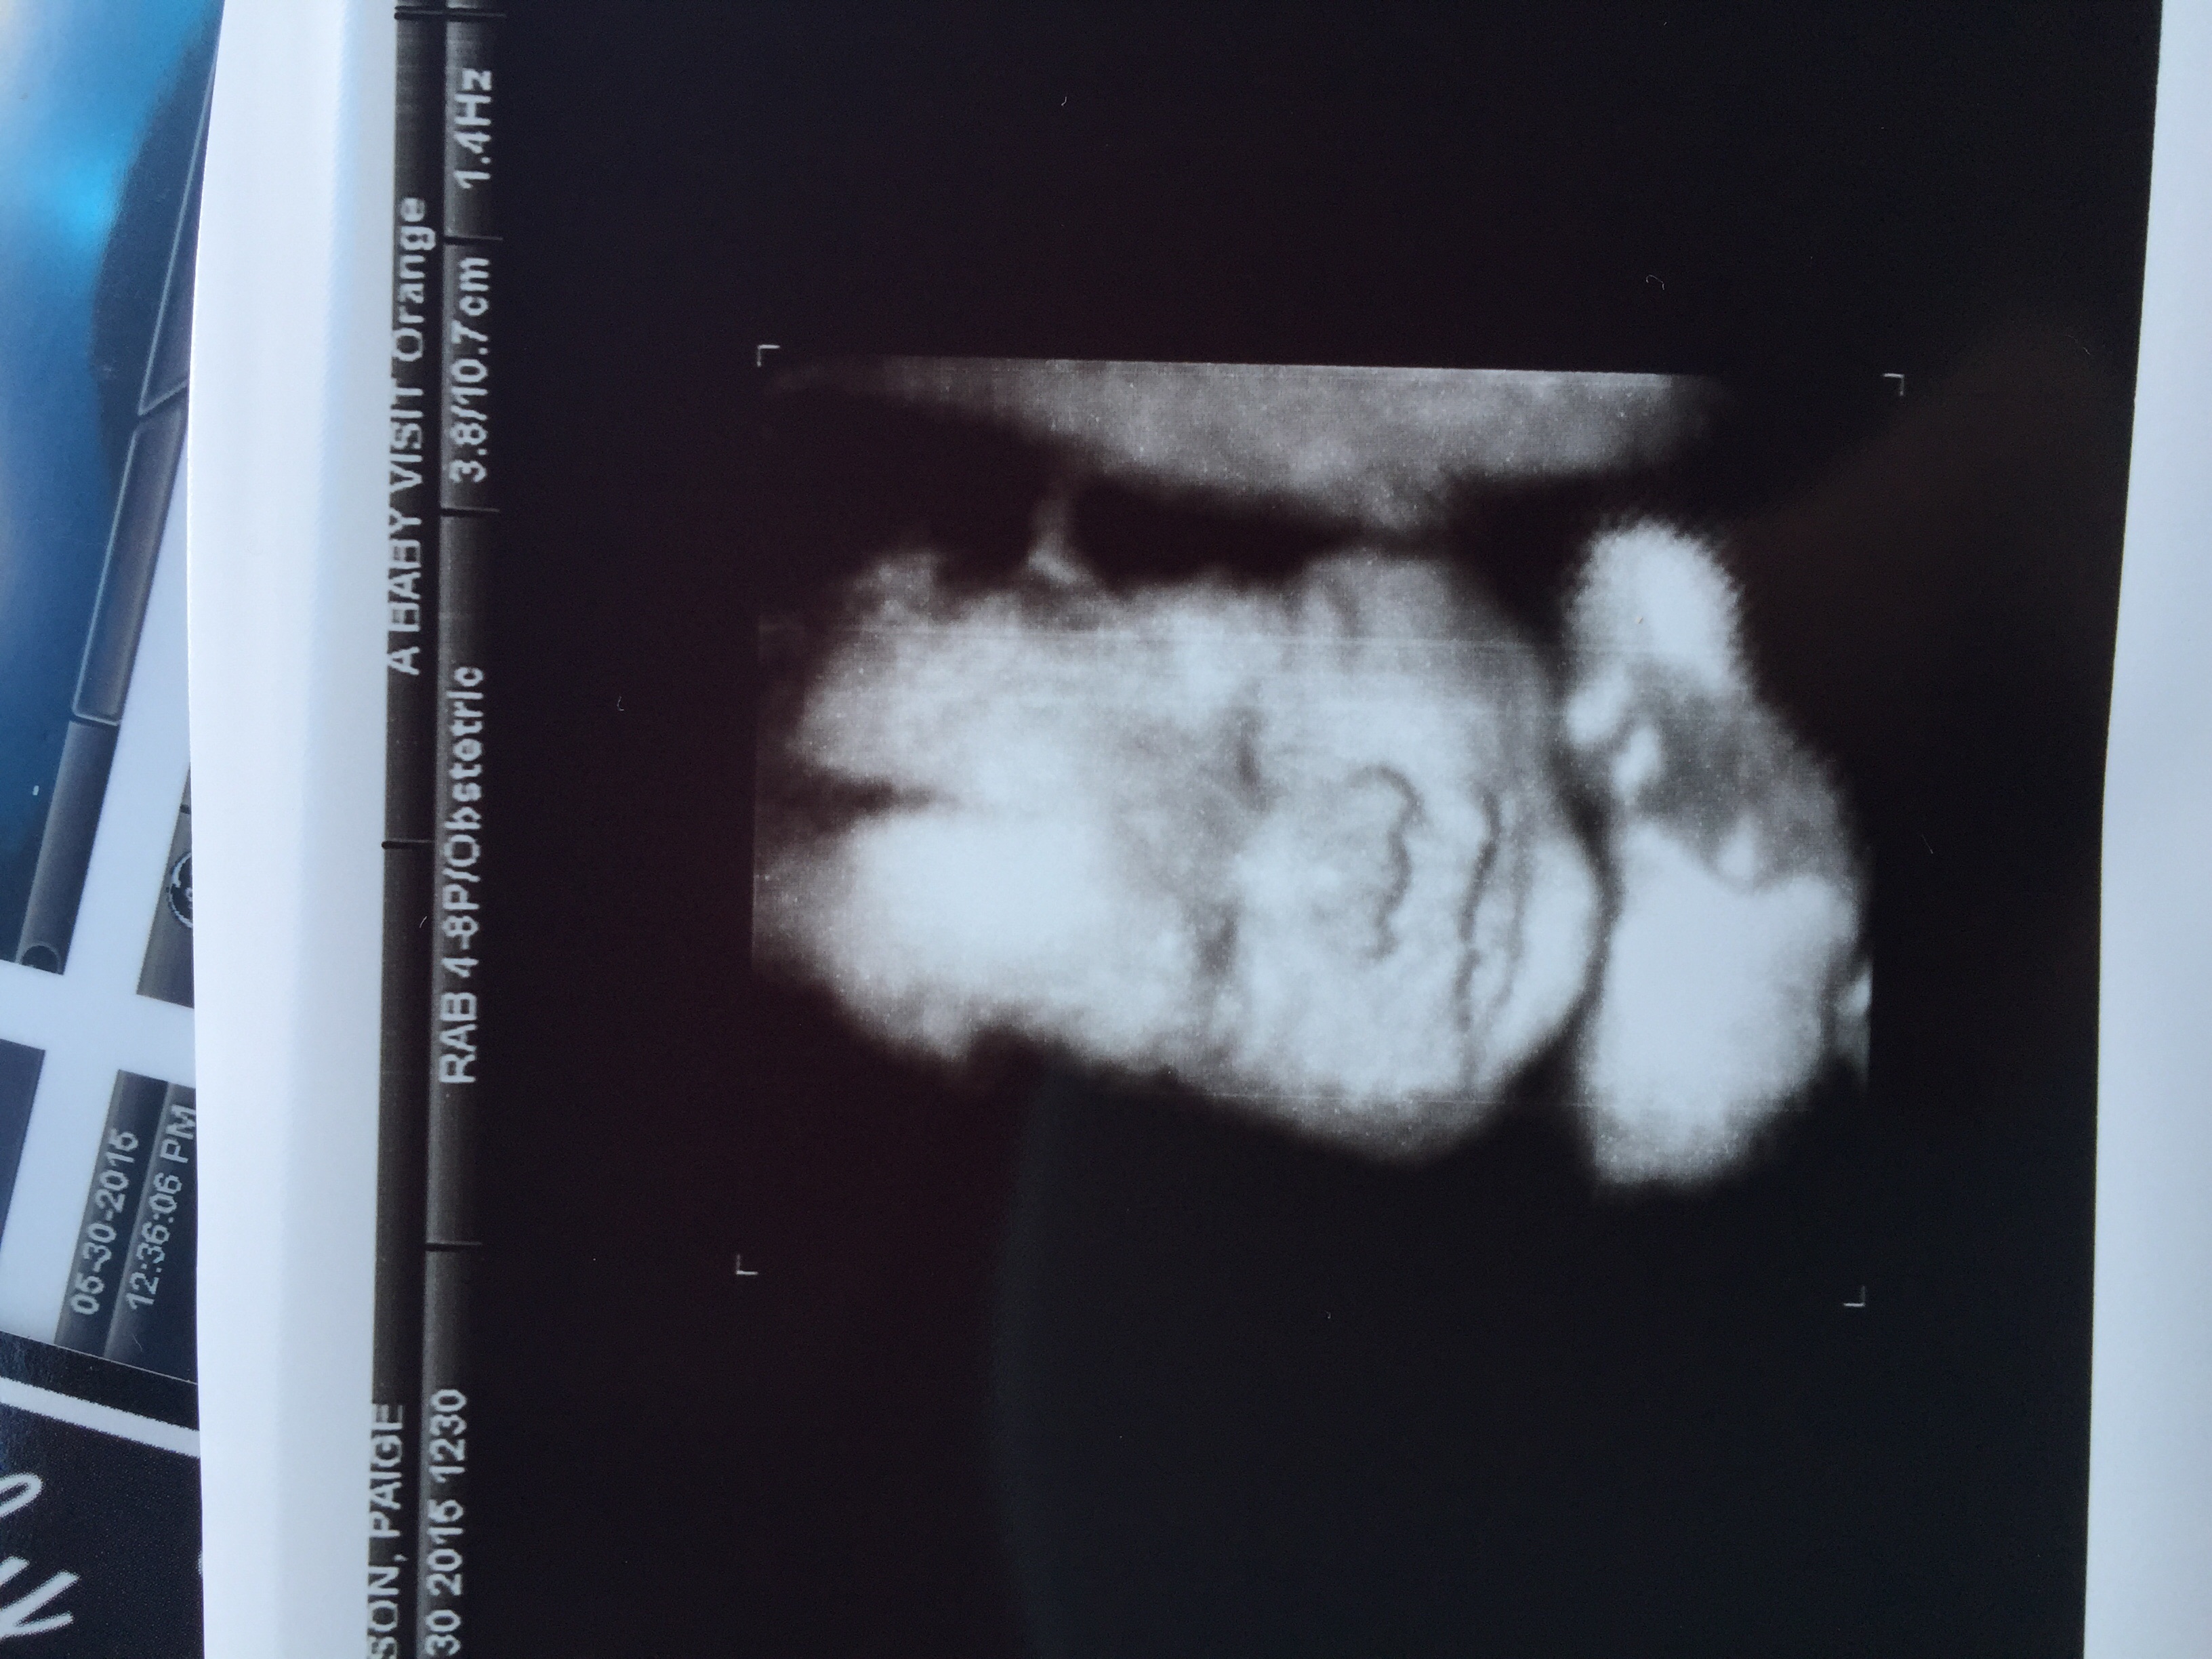

Share your 3D pics!!!!